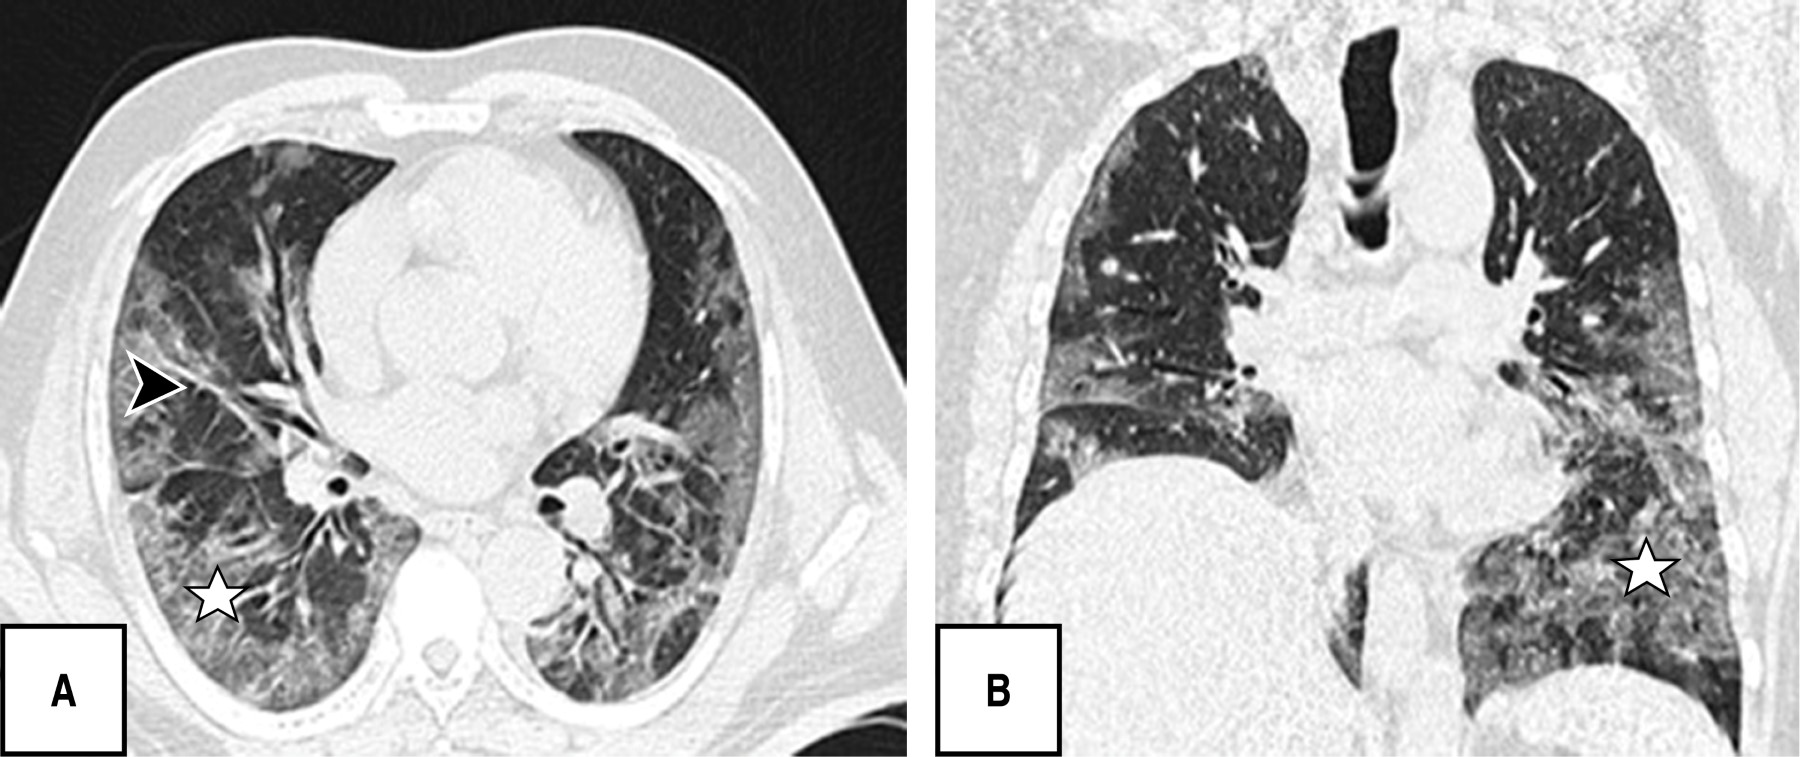

During the tomographic evaluation, the most frequent pulmonary patterns were: cobblestone pattern (120 [80.5%]), pleuroparenchymal bands (118 [79.2%]) and ground glass pattern (110 [73.8%]), reticular pattern (82 [55%]), and in lower percentage vascular dilatation (56 [37.6%]) and consolidated pattern (52 [34.9%]) (Figures 1, 2, 3 and 4).

It is noteworthy that most of the patients in this research presented in a chronic/advanced phase of the disease, finding as predominant patterns the cobblestone (120/149; 80.5%), pleuroparenchymal bands (118/149; 79.5%) and in third place ground-glass pattern (110/149; 73. 8%), without identifying any case with findings of atoll, pneumothorax or twinning tree, other studies do report ground glass opacities as the predominant finding followed by the consolidation pattern and in this regard pleural effusion, pericardial effusion, lymphadenopathy, cavitation, the reverse halo or atoll sign and pneumothorax are rare, but can be observed with the progression of the disease.19-21